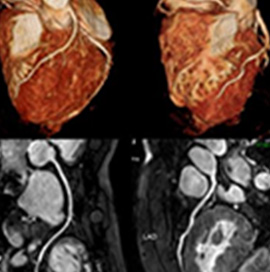

当院では心臓 CT・MRI 検査によって冠動脈を詳細に評価することができます。

「狭心症・心筋梗塞」は心臓の血管(冠動脈)が狭くなることで起こります。 当院では心臓 CT・MRI 検査によって冠動脈を詳細に評価することができます。